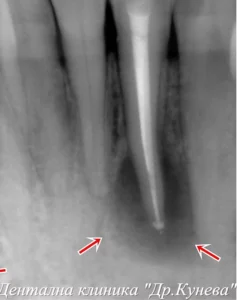

Кариесите се появяват на определени места:   В допълнение към местоположението на самия зъб, кариесите могат да засегнат и различни видове…